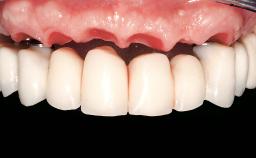

Iliac-Crest Block for Vertical and Horizontal Space Filling in the Anterior Maxilla

A 31-year-old man presented to our clinic 30 days after a motor vehicle accident in which he had suffered a dentoalveolar fracture in the anterior maxilla, including avulsion of teeth 12 and 11 and luxation of tooth 21. He was first treated on the night of the accident in a small city hospital with no oral and maxillofacial surgeon on the staff. A wired retention had been applied and the teeth repositioned to the best of the clinicians’ abilities. When he first presented to our care, the patient showed extrusion of teeth 12 and 11 associated with gingival recession due to bone loss in the anterior maxilla, and the stainless steel wires were still present.